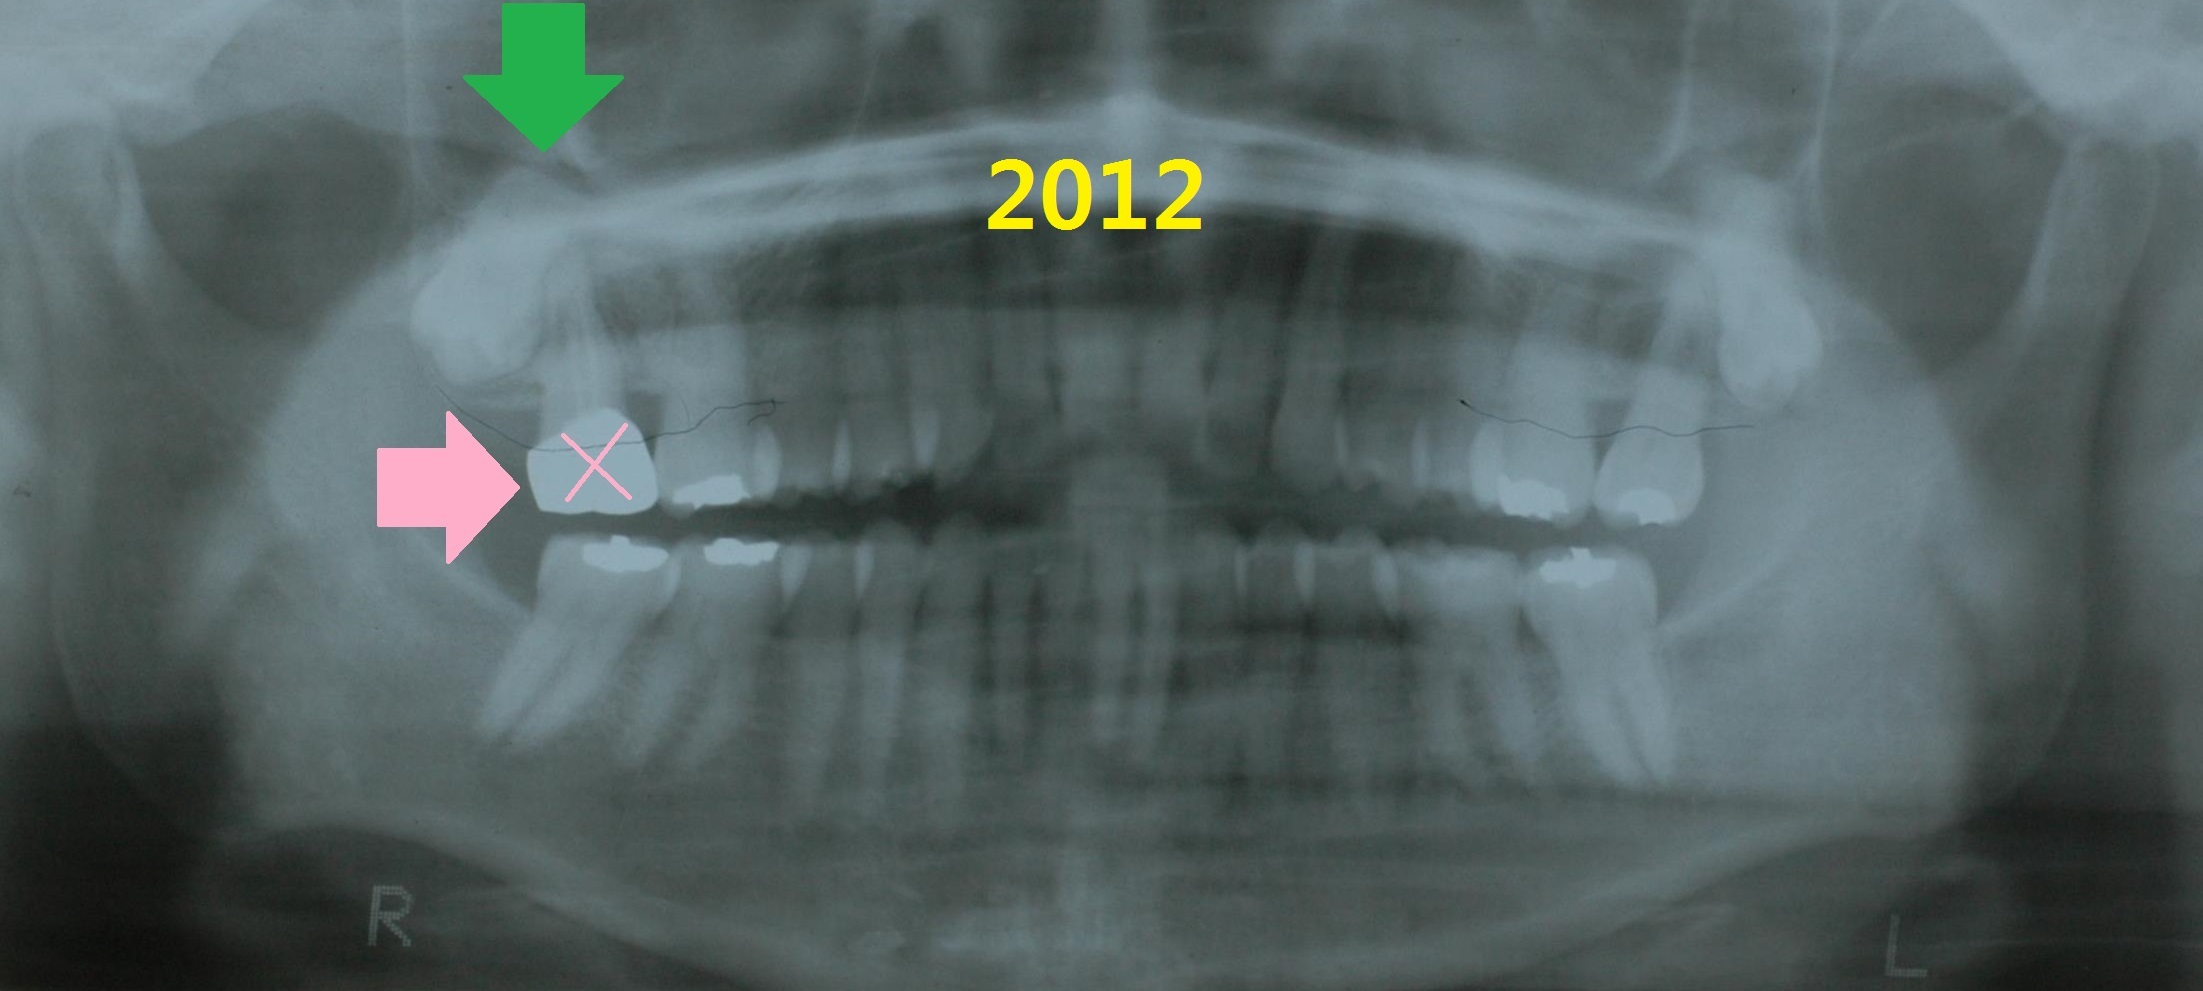

2012년(57세), 위 오른쪽 크라운 되어 있는 치아가 흔들려서 치과에 내원

발치함.

임플란트 하지 않고 지켜보자고 함.